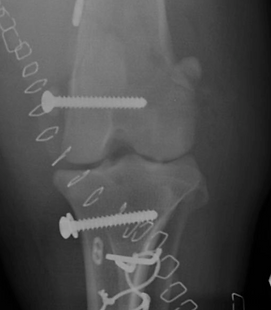

Treatment options for dislocations and ligament injuries range widely, depending on severity, location, and underlying causes. They include:

The outlook for recovery from dislocations and ligament injuries varies widely based on the joint involved, severity,

and treatment approach. Some dislocations have a good prognosis without surgery, while others may be too severe to save the limb.

Surgical technique, proper implant selection, and diligent post-operative care all play major roles in achieving the best possible outcome.